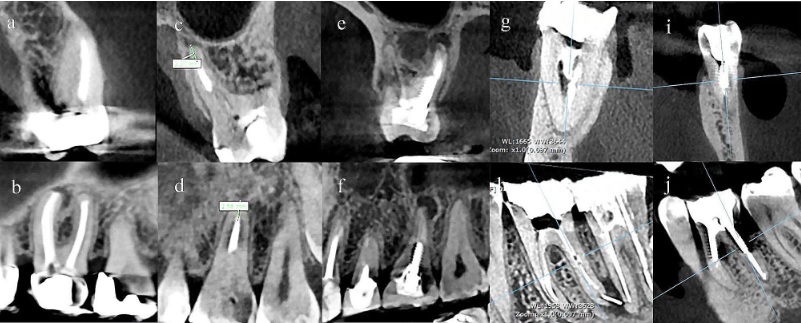

The association of endodontic prognostic factors with the presence of periapical lesion, its volume, and bone characteristics in endodontically treated molars: a cross- sectional study